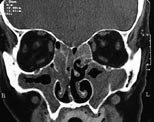

Pasienten . En 67 år gammel mann med kjent atopisk disposisjon og behandlingskrevende astma bronchiale ble henvist til Øre-nese-halsavdelingen, Nordland Sentralsykehus, etter mangeårige plager med nasalstenose. Pasienten var usikker på om han hadde fått fjernet nasale polypper tidligere. Han hadde også i perioder vært plaget med rhinoré og man mistenkte en allergisk rhinitt. Koronale CT-bilder tatt i juli 1999 viste pansinusitt og nasal polypose (fig 1).

Ved avtalt kontroll ved poliklinikken sju uker etter operasjonen fant man ved CT ingen tegn til pneumocephalus. Pasienten hadde nå ingen nasalstenose eller rhinoré (fig 3).